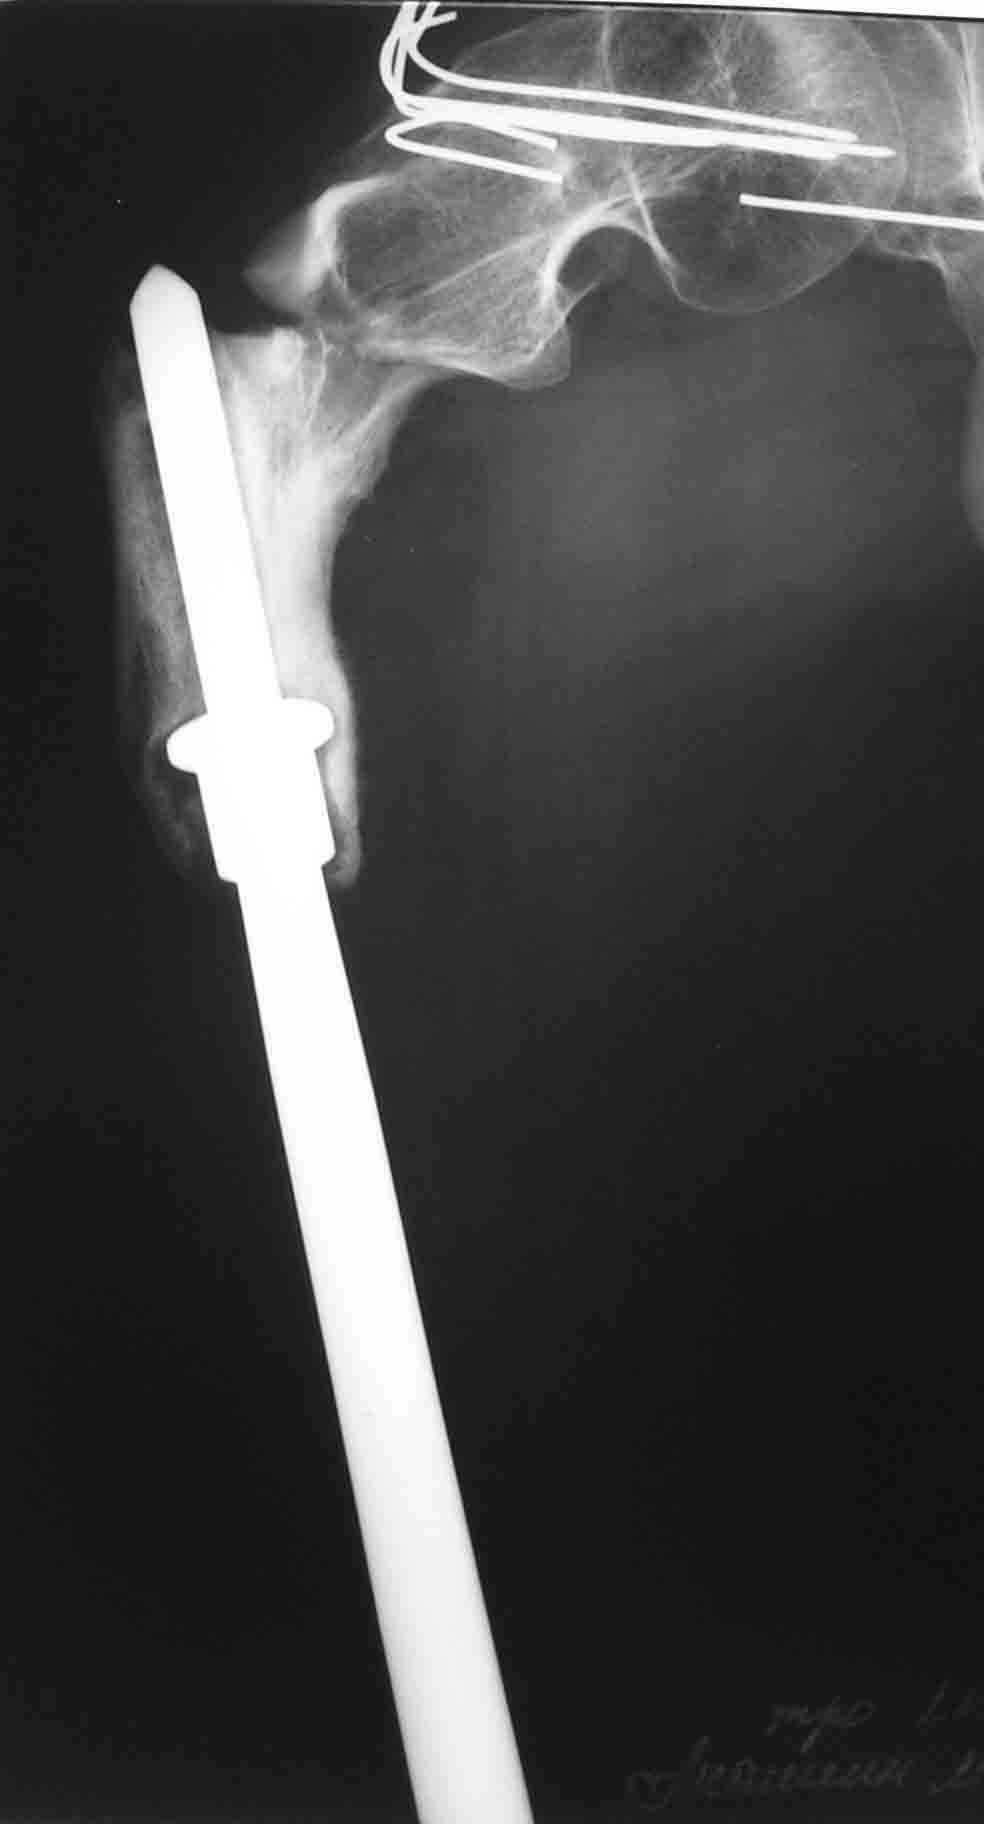

Re: Подвертельный перелом

Пациент находится в Вологде. Это 500 км к северу от Москвы.

До травмы передвигался самостоятельно с дополнительной опорой (трость). Имеется укорочение ноги 15 см.